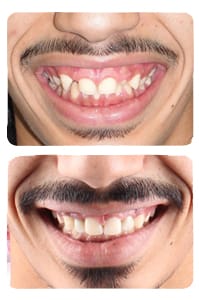

ابتسامة-32

أسنان منطمرة في العظم, أضراس خلفية مائلة, ابتسامات, ازدحام أسنان, بروز أسنان أمامية علوية, بروز مضاعف للأسنان الأمامية, عضة عميقة, عضة معكوسة أمامية, عضة معكوسة خلفية, عضة مفتوحة, فراغات بين الأسنان, نقص في سن أو عدة أسنان

ابتسامة-31

أسنان منطمرة في العظم, أضراس خلفية مائلة, ابتسامات, ازدحام أسنان, بروز أسنان أمامية علوية, بروز مضاعف للأسنان الأمامية, عضة عميقة, عضة معكوسة أمامية, عضة معكوسة خلفية, عضة مفتوحة, فراغات بين الأسنان, نقص في سن أو عدة أسنان